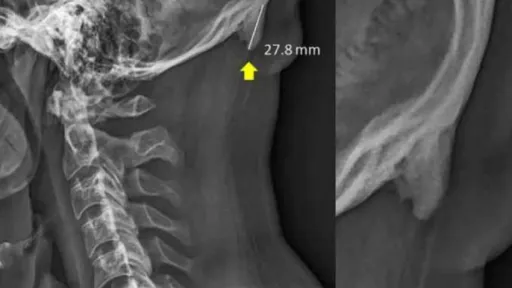

Studiul a fost realizat anul trecut, fiind din nou adus din nou în atenţia publicului, ca urmare a unui articol al celor de la BBC, care vorbeşte despre ”felul în care viaţa modernă transformă scheletul uman”.Tehnologia acţionează şi asupra scheletului uman, conform cercetătorilor.Ei au descoperit că aceste creşteri osoase sunt cauzate de înclinarea în faţă a capului, care mută greutatea de pe coloana vertebrală pe muşchii aflaţi pe partea din spate a capului, cauzând astfel o creştere a oaselor în ligamentele şi tendoanele conectate. Transferul de greutate în urma căruia apar aceste ”coarne” poate fi comparat cu felul în care pielea se îngroaşă şi se transformă într-o bătătură, ca răspuns la presiune sau abraziune.Unul dintre autorii studiului, chiropracticianul David Shahar, avertizează că această formaţiune constituie o deformare serioasă a posturii şi poate cauza dureri de cap şi dureri în partea superioară a spatelui şi în zona cefei, scrie adevarul.ro.El a fost surprins şi de mărimea pe care o ating aceste excrescenţe, majoritatea depăşind 10 milimetri, cu cea mai mare dintre ele atingând chiar 27,8 milimetri.Munca cercetătorilor a început cu trei ani în urmă, în Queensland, în urma unor scanări cu raze X ale zonei gâtului care au scos la iveală apariţia acestor ”coarne”, numite osteofite. Până atunci, prezenţa acestora era considerată a fi rară, însă Shahar a observat că ele se găseau în special pe scanările efectuate persoanelor tinere, deşi se credea că ele se formează doar la persoane în vârstă, datorită efortului şi presiunii continue asupra scheletului în timpul vieţii.”Aceste formaţiuni s-au dezvoltat într-o perioadă mai lungă, astfel încât cei care suferă de ele au aplicat probabil o presiune mare asupra zonei încă din copilărie” a explicat Shahar, citat de Washington Post.Faptul că această creştere a oaselor are loc pe o durată lungă de timp înseamnă şi că aceasta poate fi prevenită printr-o îmbunătăţire a posturii. Shahar sugerează că şcoala ar putea să îi înveţe pe copii reguli simple ale posturii, precum felul în care ar trebui să doarmă, pentru a anula efectele cauzate de folosirea telefonului mobil în timpul zilei.”Puteţi pune mâna pe zona respectivă din spatele capului, deasupra cefei. Cei care au aceste coarne le vor putea, cel mai probabil, simţi” a încheiat el.Până la apariţia unor examinări şi cercetări concludente pe această temă, este greu să realizăm o corelaţie definitivă între creşterea acestor coarne şi folosirea prelungită a telefonului mobil. Însă pericolul nu trebuie subestimat.